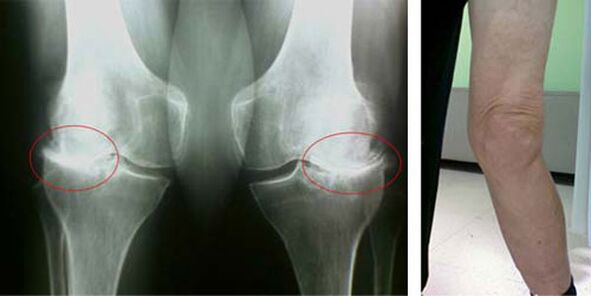

In a healthy knee joint, cartilage is a type of lining that does not allow the bones to touch, therefore eliminating the possibility of damage from walking. Sick cartilage is not able to cope with this function, therefore signs of stiffness in the joint appear during movement, accompanied by pain. This condition becomes permanent due to internal pathological changes, when the thinning of cartilage tissue leads to thickening of the bone and creates conditions for the appearance of bone spurs - osteophytes, which provoke acute pain.

The initial stages of the appearance of such a pathology as arthrosis of the knee joint do not manifest themselves visually in any way. However, after a certain time, the patient notices signs of knee deformity, as well as a characteristic curvature along the axis of the lower leg (directed inward). There is also a crunch when you need to bend your leg.

The presence of pain, limited movement in the knee causes a person to consult a doctor and undergo an examination. To do this, you need to pass tests and take an x-ray of the diseased joint. If these measurements are not enough to confirm osteoarthritis of the knee joint, an MRI is performed. Based on the data collected, the doctor chooses the best treatment methods.